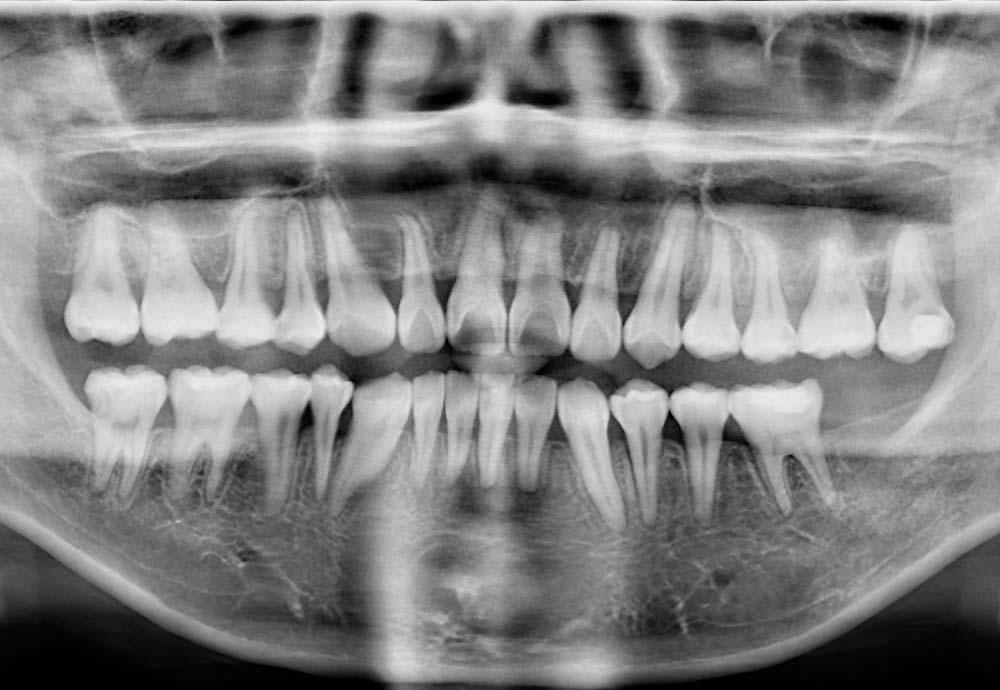

Wisdom teeth may need to be removed if they are impacted, causing pain, swelling, infection, or damage to nearby teeth.

Other reasons include preventing future dental problems such as decay, gum disease, cysts, or crowding of your existing teeth.

Wisdom tooth removal is generally safe, but like any surgical procedure, there are some risks such as nerve irritation and infection.

In rare cases, lower wisdom teeth may be close to a nerve, which could cause temporary numbness. To improve safety, we use Piezo-assisted surgery and laser disinfection, which help protect nearby tissues and support faster healing.